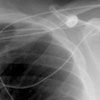

After the patient received his first cycle of cyclophosphamide, doxorubicin, vincristine, and prednisone (CHOP) chemotherapy, a chest film showed a right-sided pleural effusion (A). Thoracentesis was performed. The pleural fluid protein level was 5.0 g/dL, and the lactate dehydrogenase level was 124 U/L. The triglyceride level was elevated (2800 mg/dL). Flow cytometry of the pleural effusion showed no evidence of a monoclonal B-cell process. The patient required ultrasound-guided thoracentesis for each of the next 3 cycles of CHOP chemotherapy; the chylous pleural fluid obtained at thoracentesis is shown (B). He then underwent a right thoracoscopy, mini-thoracotomy with ligation of the thoracic duct, and doxycycline talc pleurodesis. There were no further pleural effusions.